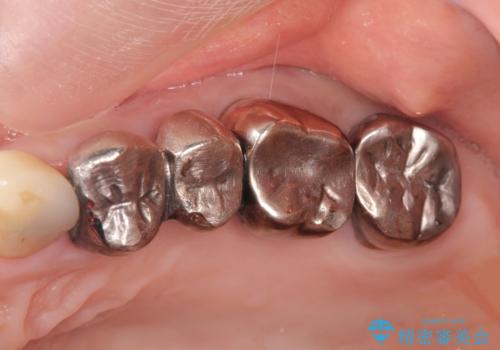

銀歯の除去 長期的な未来を見据えた虫歯治療

- 「長年使ってきた銀歯からなんとなく臭いがするので治したい、今後しっかり噛めるような歯の治療を受けたい。」

と希望され来院されました。

銀歯を除去したのち、虫歯を丁寧に除去し、歯を残せるのかどうかをしっかりと評価し、長期的な予後を見据えた虫歯治療を行っていきます。